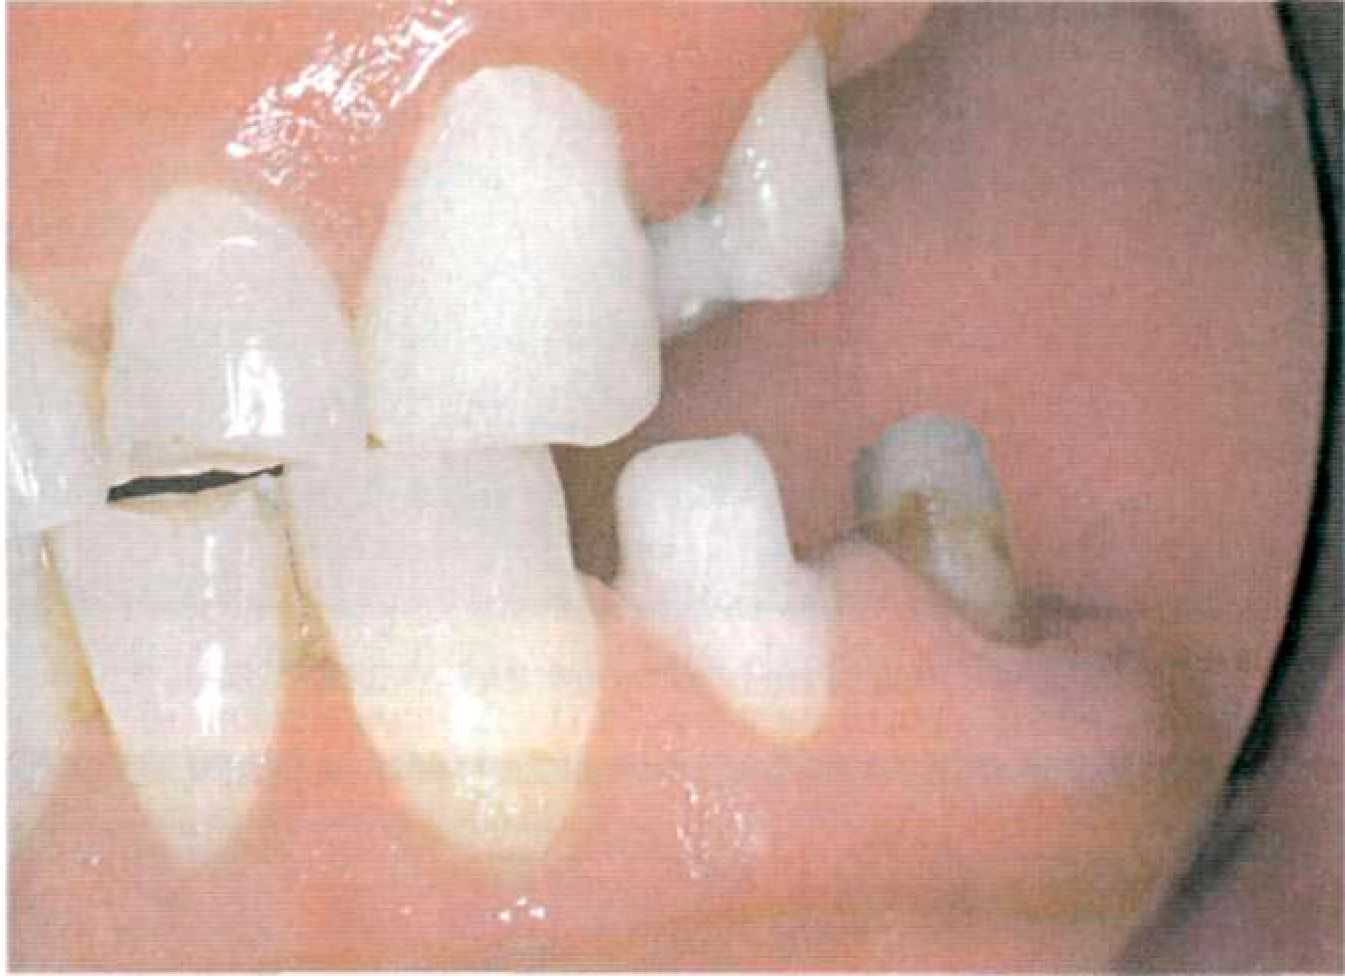

Далее снимают двухслойный или однослойный (монофазный) оттиск силиконовым оттискным материалом, препарированные зубы покрывают временными коронками (рис. 105). Определяют центральную окклюзию с формированием протетической плоскости. Этап 3. В лаборатории зубной техник изготавливает разборную модель из супергипса, гипсует модели в артикулятор и моделирует каркас коронок опорных зубов с патрицей или матрицей аттачмена, установленной в параллелометре (рис. 106). Обязательным условием при использовании жесткого замкового крепления является фрезерование опорных коронок (рис. 107).